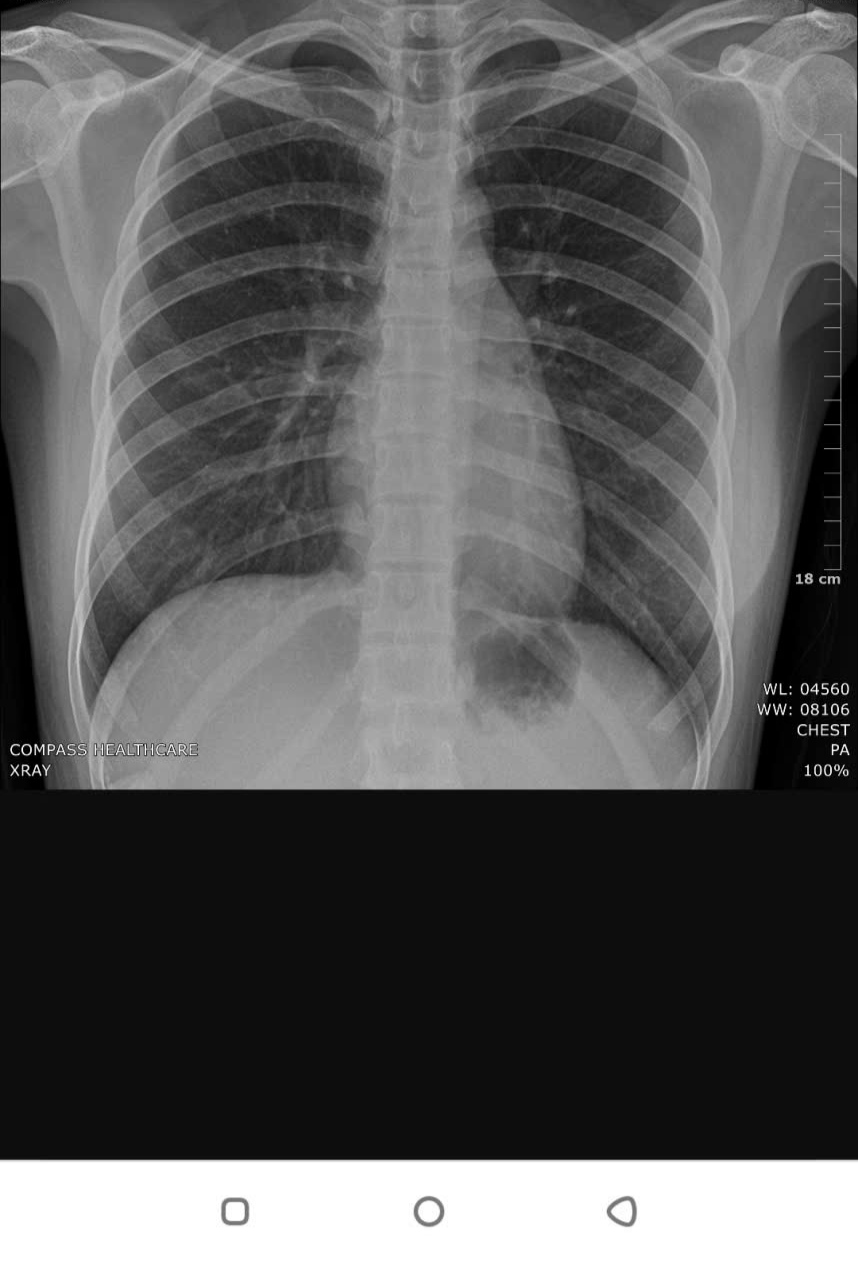

Dạ cho e hỏi có 1 cục ở dưới phổi là cục gì vậy ạ

Dạ các bác sĩ vui lòng cho e hỏi cái cục dưới phổi là cục gì ạ , em xin cảm ơn các bác ạ.

Em đánh dấu vị trí em nghi ngờ

Dạ bác cho em hỏi cục này là gì vậy ạ , em cảm ơn bác rất nhiều ạ

Bình thường có gì đâu em

Không bất thường nhé